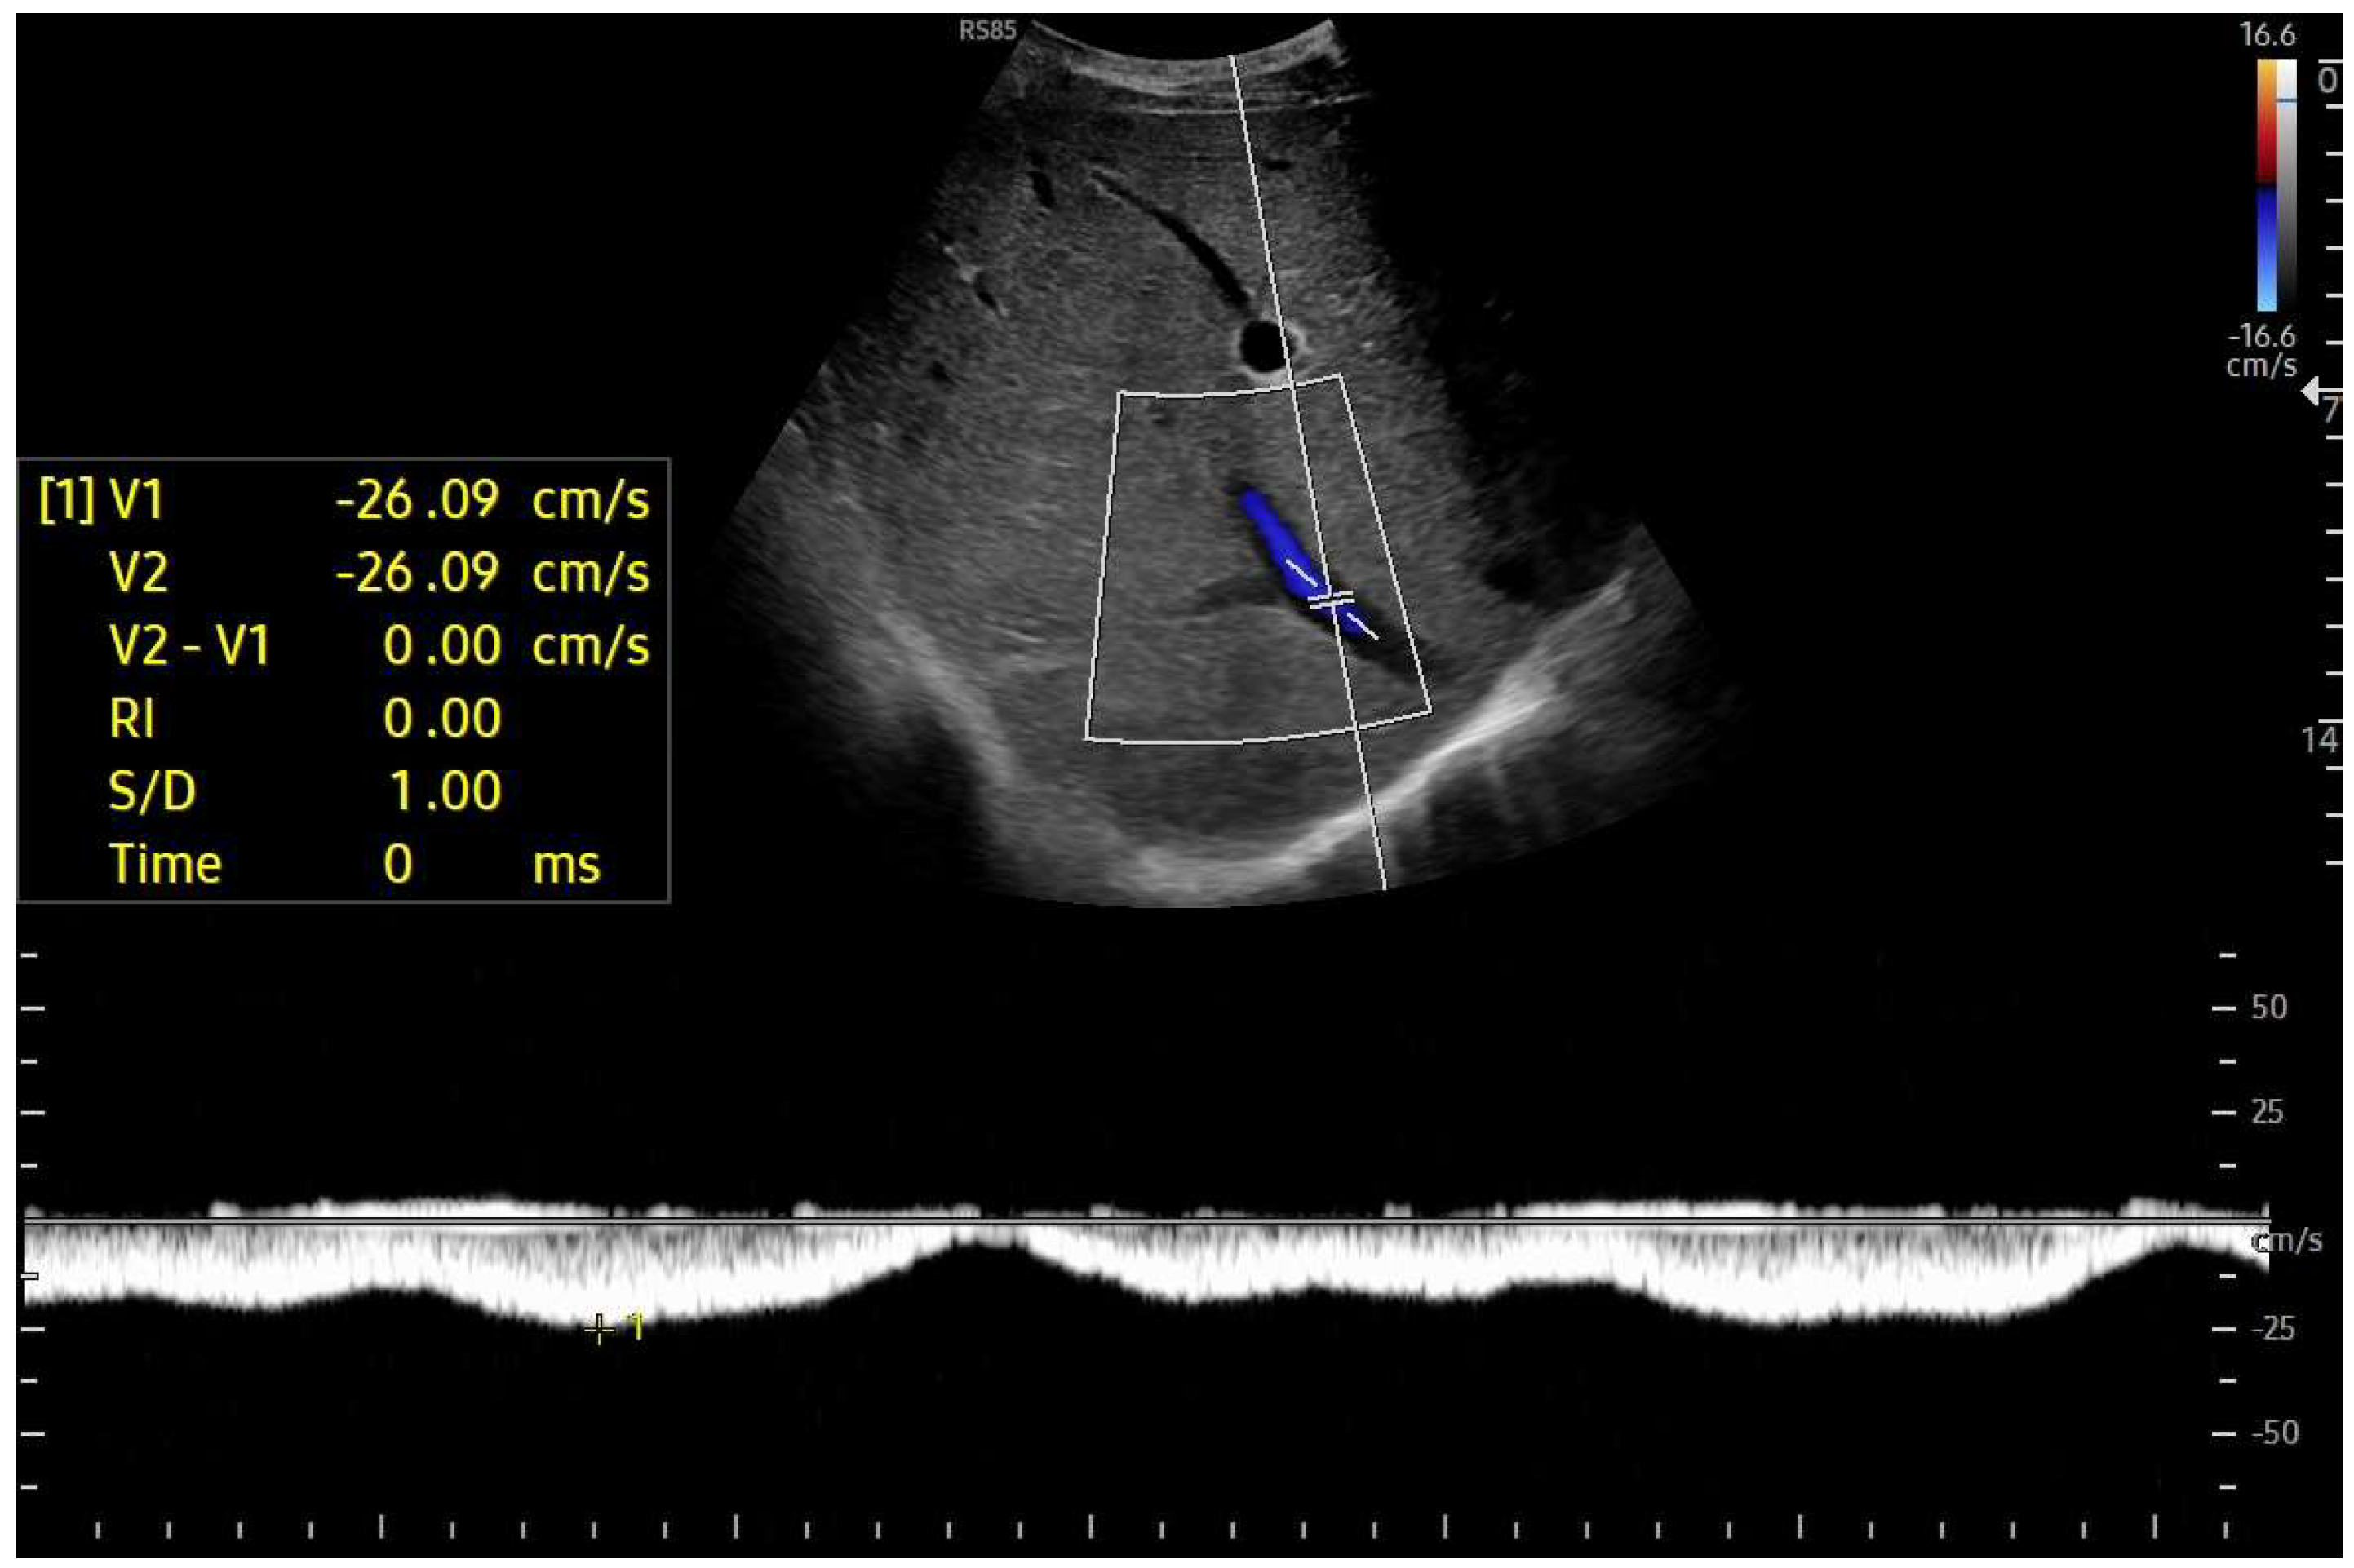

Doppler patterns in Fontan patients resemble those observed in chronic liver disease, including reduced portal flow velocity (mean flow velocity < 14 cm/s) [56]. The Fontan procedure inevitably alters hepatic venous waveforms on Doppler US (Figure 10, Figure 11, Figure 12 and Figure 13). Inverted portal flow has a specificity of 100% for diagnosing PHTN [57] (Figure 12). The hepatopetal phase pattern in the hepatic vein differs between patients with total cavo-pulmonary anastomosis (including both lateral tunnels and extracardiac conduits) and those with atrio–pulmonary connection [58,59,60]. In atrio–pulmonary connection, hepatopetal flow is preserved (Figure 10), reflecting the exclusion of atrial contribution to venous circulation, whereas in total cavo-pulmonary anastomosis, flow reversal (Figure 11) occurs only during early expiration. Similarly to congestive heart failure, hepatic veins and the IVC are dilated, with abnormally increased hepatic vein pulsatility, regardless of the anastomosis technique [54,61,62]. The loss of the normal three-phase Doppler pattern in hepatic veins is universal following bi-cavo-pulmonary surgery due to the absence of atrial contraction. The presence of a monophasic pattern indicates advanced liver injury [63].

Figure 10.

Doppler Ultrasound of the middle hepatic vein showing the loss of the normal three-phase pattern due to the absence of atrial contraction.

Among individuals with Fontan physiology, the hepatic veins typically show a dampened, predominantly hepatopetal monophasic waveform, reflecting the presence of long-standing hepatic congestion. Venous flow velocities are markedly reduced compared with those measured in healthy individuals [63,64]. In contrast, in later stages characterized by cirrhosis and increased hepatic stiffness, further dampening or paradoxical changes in the venous flow pattern may be observed [37,56,64].

In particular, the hepatic venous Doppler waveform offers valuable insight into hemodynamic changes over time. In the early post-Fontan period, in the absence of atrial contraction and before structural liver damage is evident, the hepatic venous flow may display a relatively blunted monophasic or biphasic waveform with reduced phasicity, reflecting the lack of pulsatility and elevated central venous pressure [37,56,64].

As FALD progresses, and especially in the setting of developing cirrhosis, the Doppler waveform may become more dampened or even flat, corresponding to the increasing stiffness of the hepatic parenchyma, reduced compliance of the vascular bed, and worsening portal hypertension [37,56,64]. Simultaneously, the hepatic veins may appear dilated in the early and mid-stages of disease due to chronic venous congestion, but may show reduced caliber in later stages as fibrosis progresses and vascular remodeling occurs [37,56,64].

Tracking these Doppler changes, from waveform morphology to vein diameter, could provide a non-invasive, dynamic marker of FALD evolution. Including representative Doppler images at different timepoints post-Fontan would help clinicians recognize these transitions and potentially stratify risk or guide surveillance intensity.